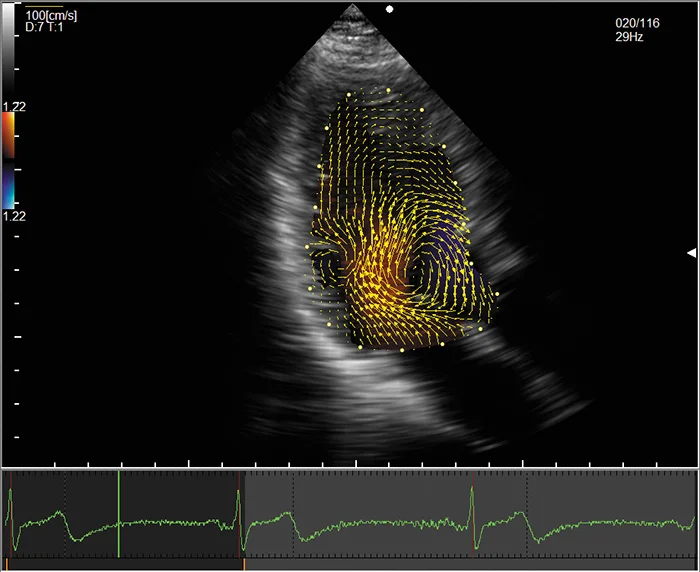

Векторное картирование кровотока

Vector Flow Mapping (VFM) является новой технологией для исследования гемодинамики. Данная технология призвана дополнить ультразвуковую кардиологическую диагностику, предоставляя новую диагностическую информацию о скорости и направлении движения потоков крови.

Основной областью применения векторного картирования кровотока являются турбулентные потоки в камерах сердца. Именно такие потоки отвечают за распределение кинетической энергии, необходимой для перенаправления потоков крови и работы клапанов сердца.

Векторное картирование является основой для ряда дополнительных методов, таких как анализ рассеяния энергии (Energy Loss), анализ изменения давления (Relative Pressure), измерение сдвиговой нагрузки крови на стенки сердца (Wall Shear Stress) и автоматизированное измерение параметров потоков. Доступно сочетанное отображение информации, полученной от разных методов анализа векторов.

Так как гемодинамика изменяется при наличии патологии, векторное картирование позволяет оценить тяжесть заболевания, выбрать тактику и оценить эффективность лечения, в том числе хирургического.

Преимуществами метода являются широкая доступность, простота использования и малая продолжительность.

С недавнего времени технология доступна и для сосудов: модификация VFM Vascular позволяет картировать потоки в сонных артериях и анализировать сдвиговую нагрузку на стенки сосудов в режиме Wall Shear Stress (WSS).